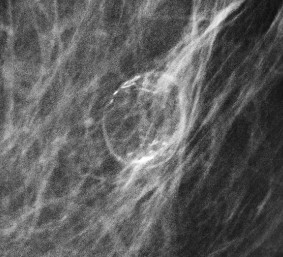

What is the best descriptor for the type of calcification that is seen with this fat-containing mass?

A. Rim calcification

Explanation: A rim calcification is composed of a continuous rim of thin (≤ 1 mm) calcification that surrounds a round or oval structure, usually with distinct internal fat density, as is true for this case. This large rim calcification has the typical appearance of fat necrosis, as can be seen in the setting of prior breast trauma or surgery (such as implant placement). Oil cysts or simple cysts (not shown in this case) can also have smaller rim calcifications. Rim calcifications are typically benign.